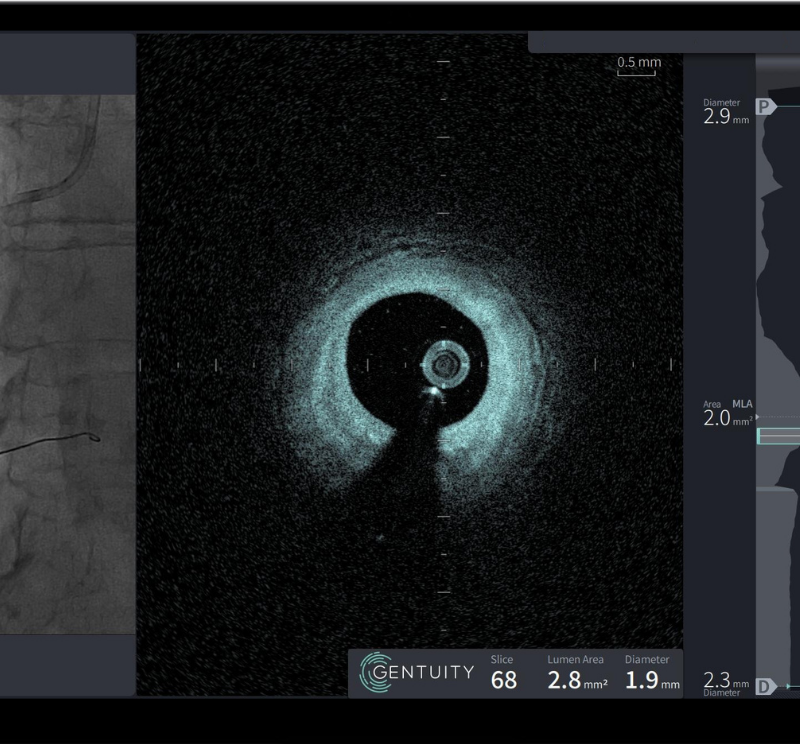

HF-OCT-Guided PCI in a Critically Narrow LAD Case Studies HF-OCT-Guided PCI in a Critically Narrow LAD